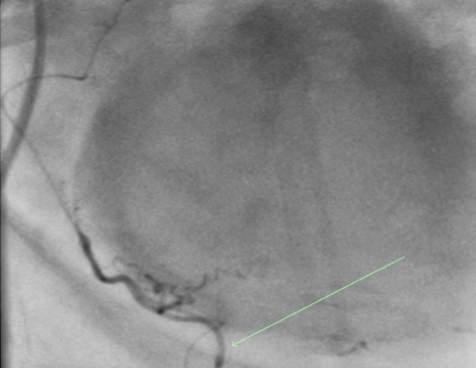

Issuu converts static files into: digital portfolios, online yearbooks, online catalogs, digital photo albums and more. Sign up and create your flipbook.